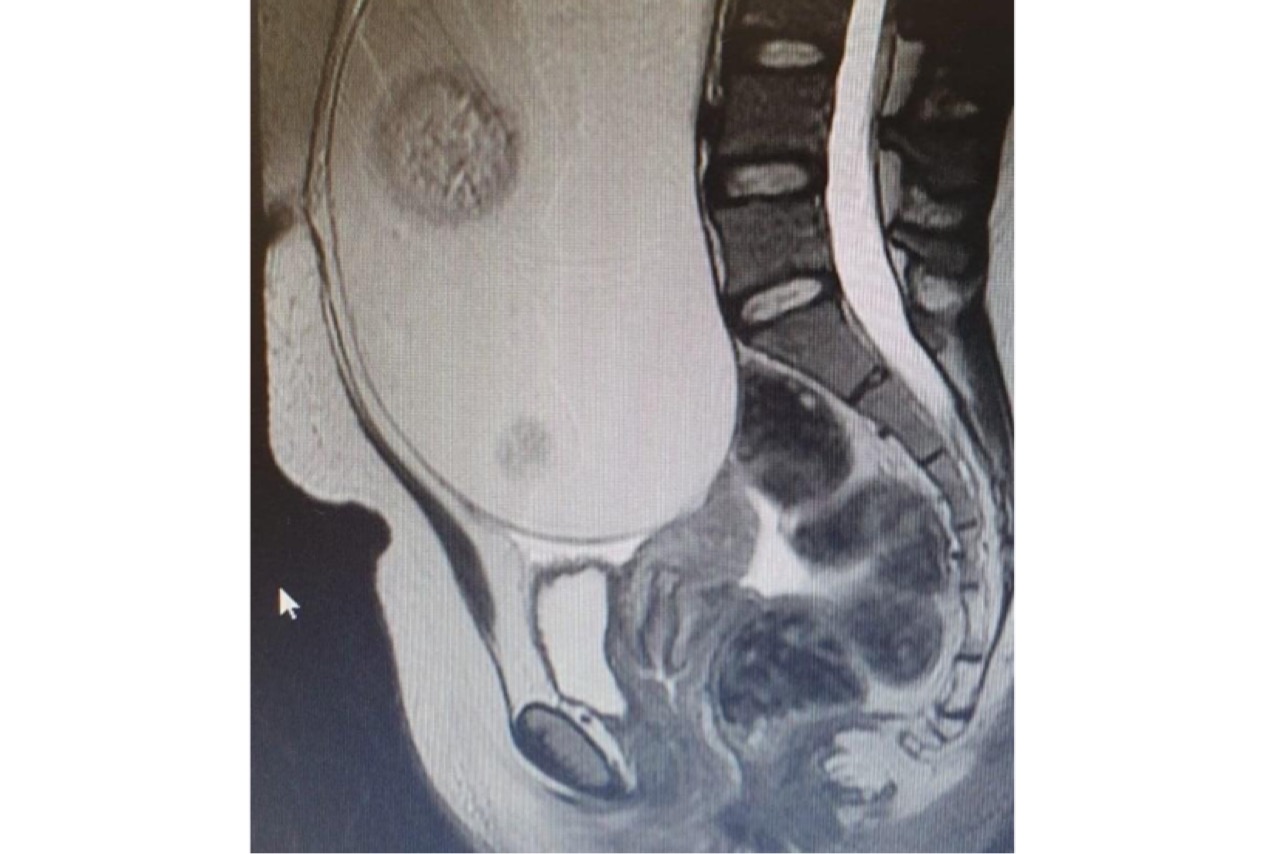

În urma consultului i s-a recomandat și un examen R.M.N, care a evidențiat tumora. Intervenția a durat două ore și jumătate fiind dificilă datorită faptului că tumora ocupa aproape în întregime cavitatea abdominală. Evoluția postoperatorie a fost favorabilă, pacienta s-a externat la două zile după operație.